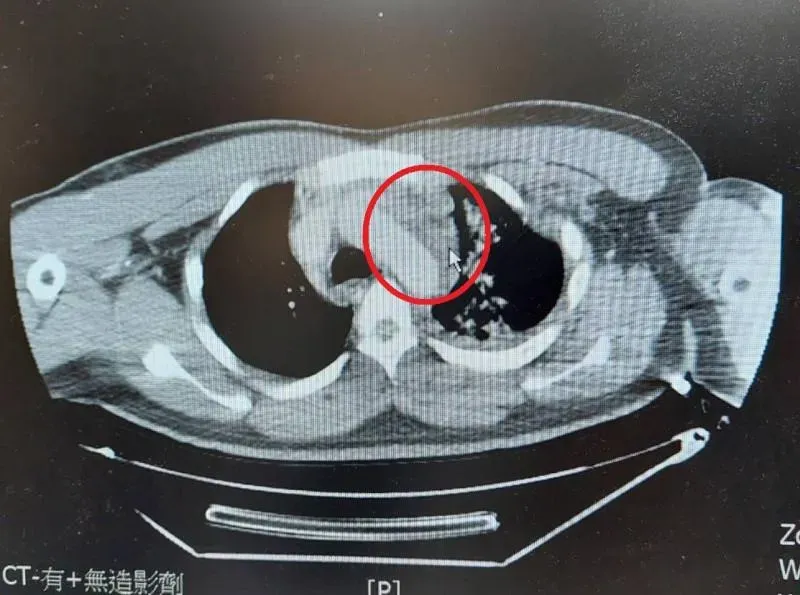

肺臟破裂

肋骨內固定手術

胸腔外科

微創手術

平等澄清醫院

杜承哲醫師

主動脈剝離

外傷性胸主動脈剝離

主動脈血管支架置放手術

大千綜合醫院

手術治療